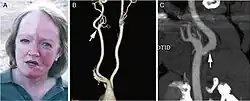

A man exhibiting the asymmetric symptoms of Harlequin syndrome. One half of the forehead is more red than the other. |

Harlequin syndrome, also known as "harlequin sign", is a condition characterized by asymmetric sweating and flushing on the upper thoracic region of the chest, neck and face. Harlequin syndrome is considered an injury to the autonomic nervous system (ANS). The ANS controls some of the body's natural processes such as sweating, skin flushing and pupil response to stimuli.[1] Individuals with this syndrome have an absence of sweat skin flushing unilaterally, usually on one side of the face, arms and chest. It is an autonomic disorder that may occur at any age.[2]